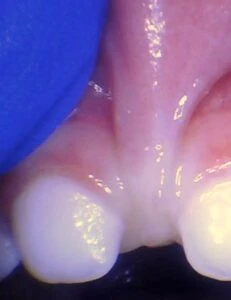

Spectrum of lip restriction in an infant

Spectrum of tongue restriction in an infant

Posterior tongue-tie in an infant seen with lifting the tongue. The posterior or “hidden”tongue-tie can cause the same symptoms including nursing pain and poor weight gain, as a to-the-tip tie in an infant